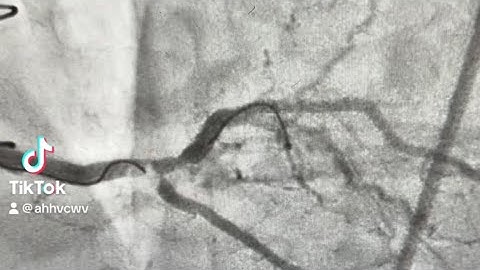

Difficult Side Branch Wiring - Prof Imad Sheiban